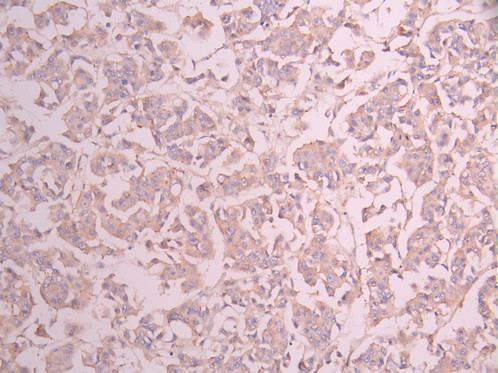

IHC image of CSB-RA010827MA1HU diluted at 1:50 and staining in paraffin-embedded human liver cancer performed on a Leica BondTM system. After dewaxing and hydration, antigen retrieval was mediated by high pressure in a citrate buffer (pH 6.0). Section was blocked with 10% normal goat serum 30min at RT. Then primary antibody (1% BSA) was incubated at 4°C overnight. The primary is detected by a Anti-Human lgG, Fcy Fragment Specific labeled by HRP and visualized using 0.05% DAB.